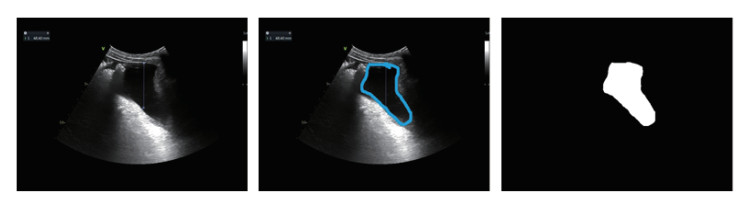

1.2 研究方法 1.2.1 图像预处理对于每张胸腹部超声出血的原始超声图像(图 1A),由超声科医生标注出血范围标注图像(图 1B),通过比较原始超声图像和标注图像之间的颜色差异,并做二值化,形态学滤波、连通区域提取操作,生成超声出血区域的掩码图像(图 1C),其中白色为出血区域,黑色为背景。

| A: 图像B: 标注C: 掩码 图 1 原始超声图像、标注图像和生成的掩码图像 |